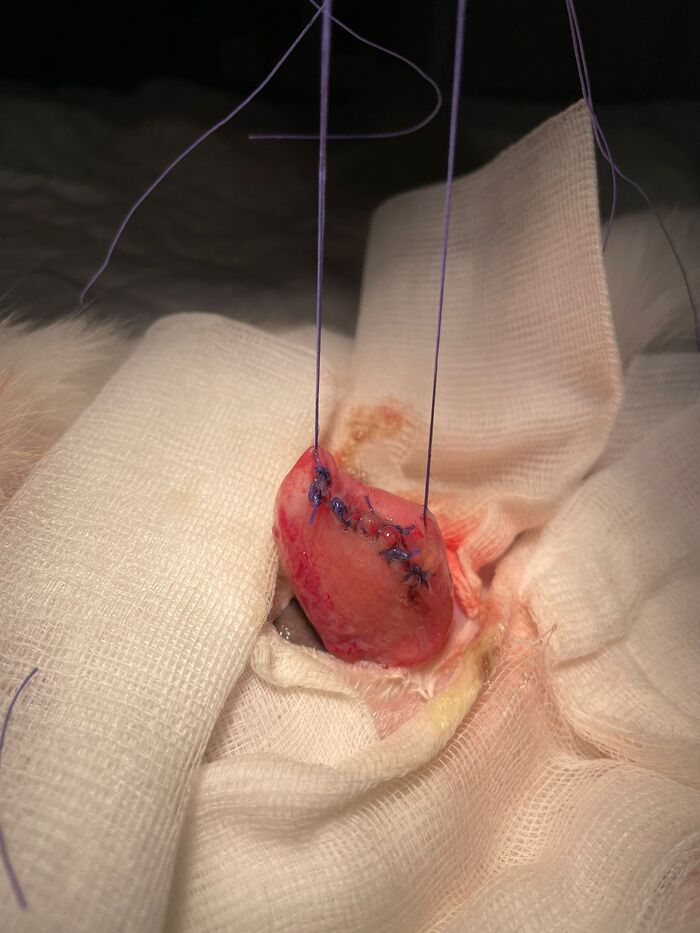

Piedras riñones / vejiga

Este es el caso de un conejito que sufría de colapso en la vejiga, como podréis ver en las radiografías tiene una cálculo enorme que le ocupa la vejiga entera, esto le producía un gran dolor y la imposibilidad de orinar, por lo que los riñones sufrían riesgo de colapso en cualquier momento. Tenía graves problemas digestivos también causados por dolor y por una parálisis en el intestino (íleo paralítico), algo que es muy grave en conejos, no podía digerir bien la comida y dejó de comer, antes de ello tuvo diarrea un tiempo.